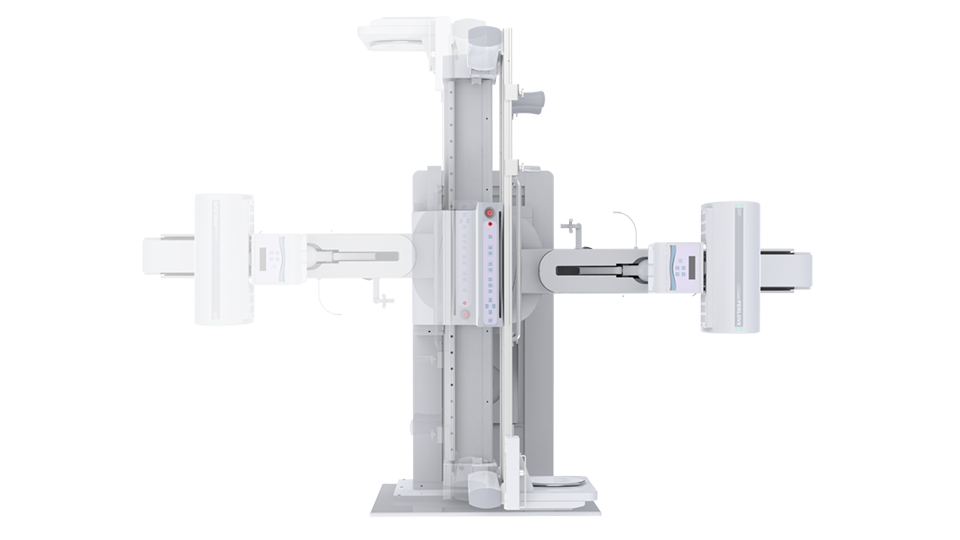

● 獨特實用的床面升降功能,有利于DR攝影及行動不便的患者上下床;

● 床面可降至與病床平行高度,既方便醫護人員平移患者,又避免對患者的二次傷害;

● 對于醫生的近臺操作也更方便,不同身高的醫生可根據需要調節床體高度,更利于醫生開展相關近臺手術。

球管傾斜攝影角度-45°~45°,滿足臨床各部位各角度的攝影需求。如:髕骨軸位、頸椎正位、骶尾椎、鼻竇瓦氏位、梅氏位等部位檢查。

拉伸自如:SID電動拉伸,最長可延伸至1.8米,滿足放射科室各種拍片距離的需求。如:GBZ 70-2015職業性塵肺病的診斷標準中對胸片拍片距離1.8米的要求。

點片裝置移動范圍大,無需患者移動就能完成全身各部位的檢查;

床面橫向移動,輕松實現機動人不動。